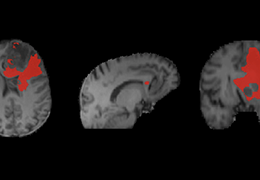

成像智能。

Eclipse 成像智能功能提供强大的处理能力和最佳质量的影像,同时减少质量错误并提高剂量效率。

凭借 AI、专有算法和先进的影像处理能力,提供出色的影像质量和无与伦比的诊断信心。